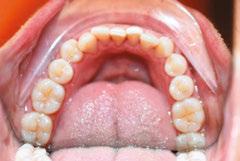

Patient J, a 39-year-old female, (Figures 1, 2, 3, 4, 5, 6) came to the office with concerns about difficulties chewing food and experiencing dry mouth upon waking up in the morning. Additionally, her partner was disturbed by her snoring. Upon examination, several issues came to light:

Figure 1: Swallowing with tongue trust

Figure 2: Anterior view before treatment

Figures 3 and 4: 3. Right side before treatment. 4. Left side before treatment

Figures 5 and 6: 5. Upper arch before treatment. 6. Lower arch before treatment